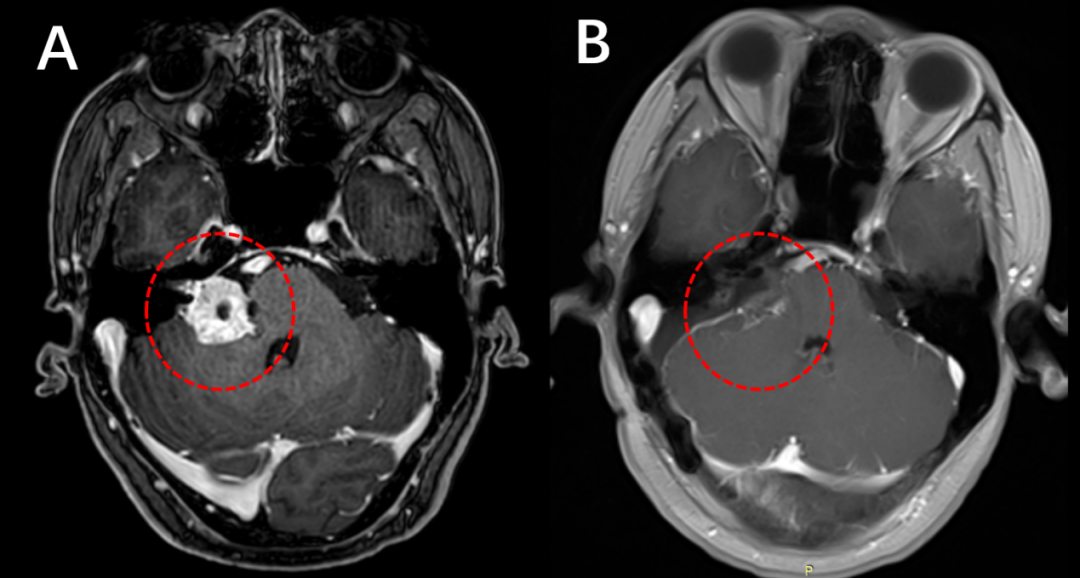

据统计,临床上57%的听神经瘤患者会出现耳鸣等症状,其中26%的患者表现为突发性耳聋。随着肿瘤的生长,患者可能出现听力下降,甚至完全消失。但也不用太恐慌,听神经瘤只要及时接受科学治疗,并不会对患者造成严重危害。只要能够及时手术,切除肿瘤,患者多数可以获得较好的预后,并且听力有可能恢复。

术前(左)和术后(右)增强磁共振检查,对比提示肿瘤完全切除(红色圈内的肿瘤消失)